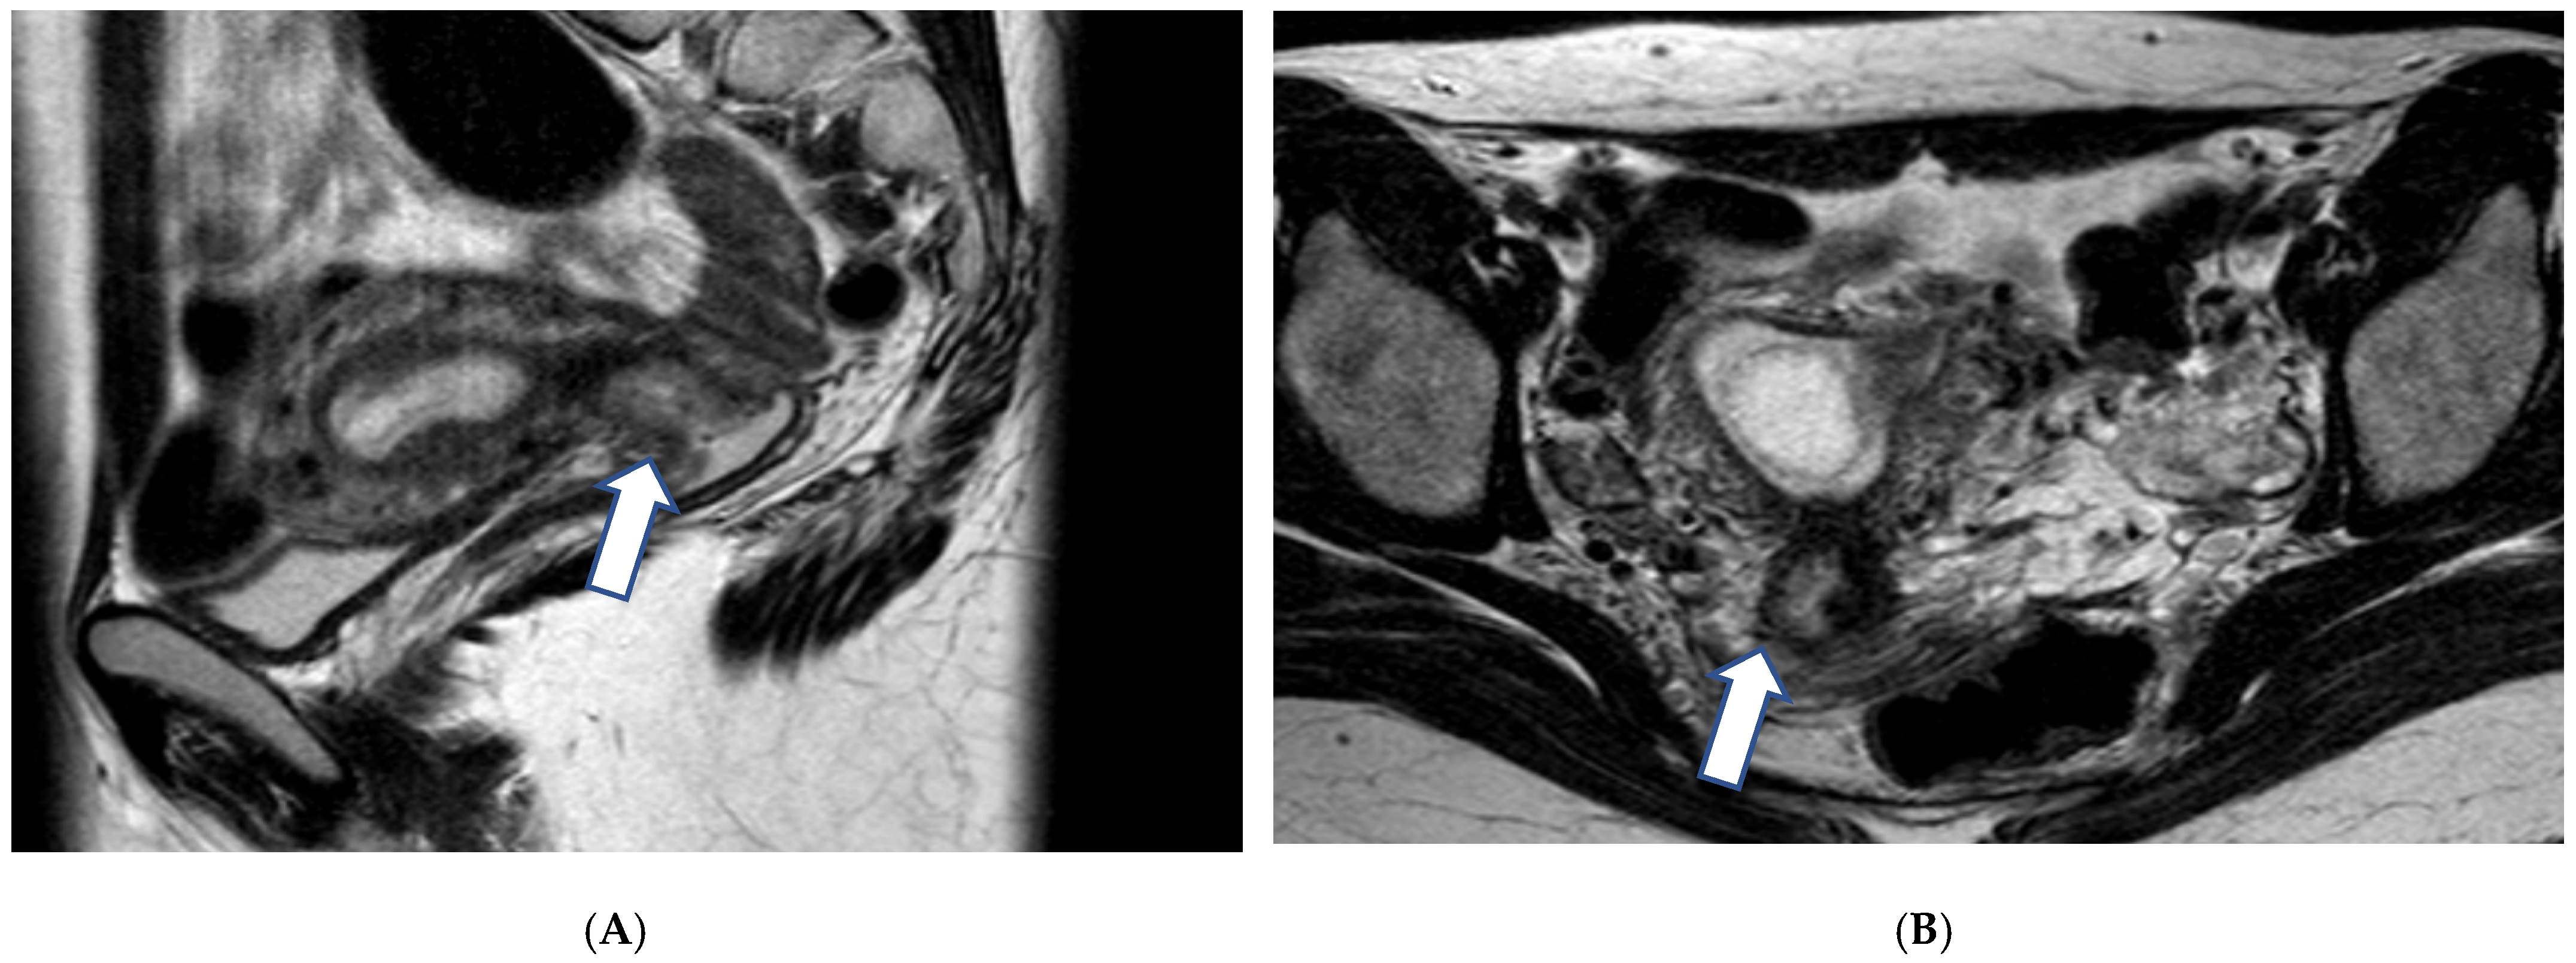

3.1.2. Imaging

- Balleyguier, C.; Fournet, C.; Ben Hassen, W.; Zareski, E.; Morice, P.; Haie-Meder, C.; Uzan, C.; Gouy, S.; Duvillard, P.; Lhommé, C. Management of cervical cancer detected during pregnancy: Role of magnetic resonance imaging. Clin. Imaging 2013, 37, 70–76. [Google Scholar] [CrossRef] [PubMed]

- Bourgioti, C.; Konidari, M.; Gourtsoyianni, S.; Moulopoulos, L.A. Imaging during pregnancy: What the radiologist needs to know. Diagn. Interv. Imaging 2021, 102, 593–603. [Google Scholar] [CrossRef] [PubMed]